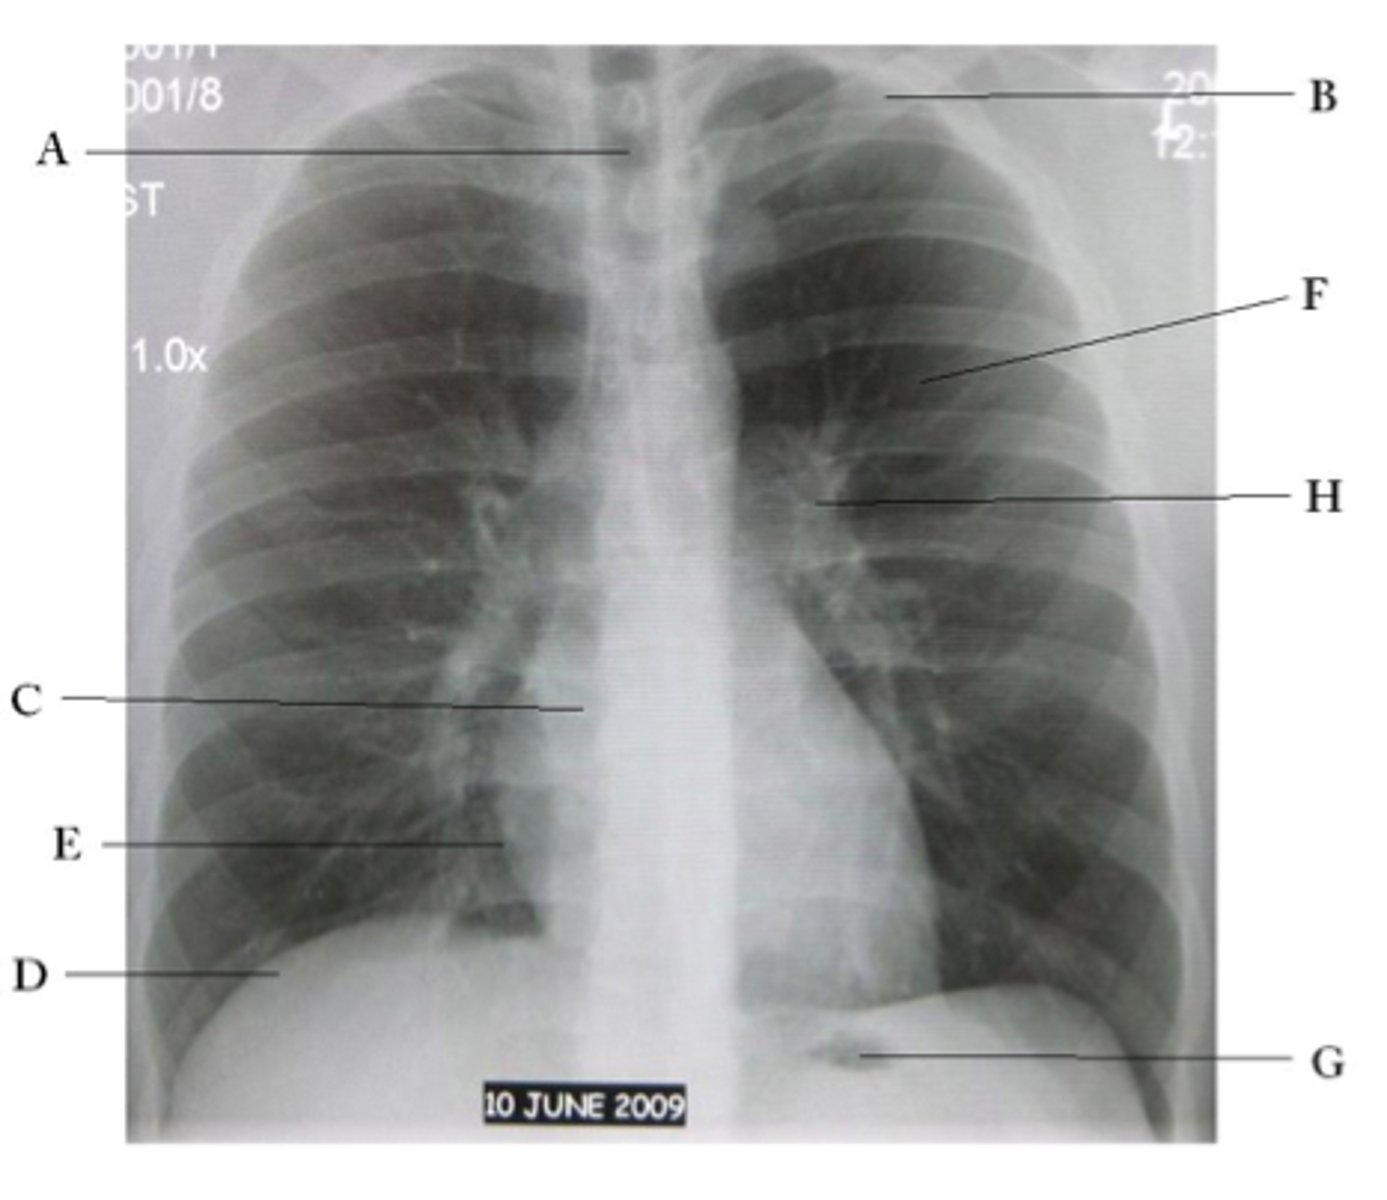

A

trachea

B

Clavicle

C

Right atrium

D

Diaphragm

E

Cardiophrenic angle

F

left upper lobe

G

gastric bubble

H

Left hilum